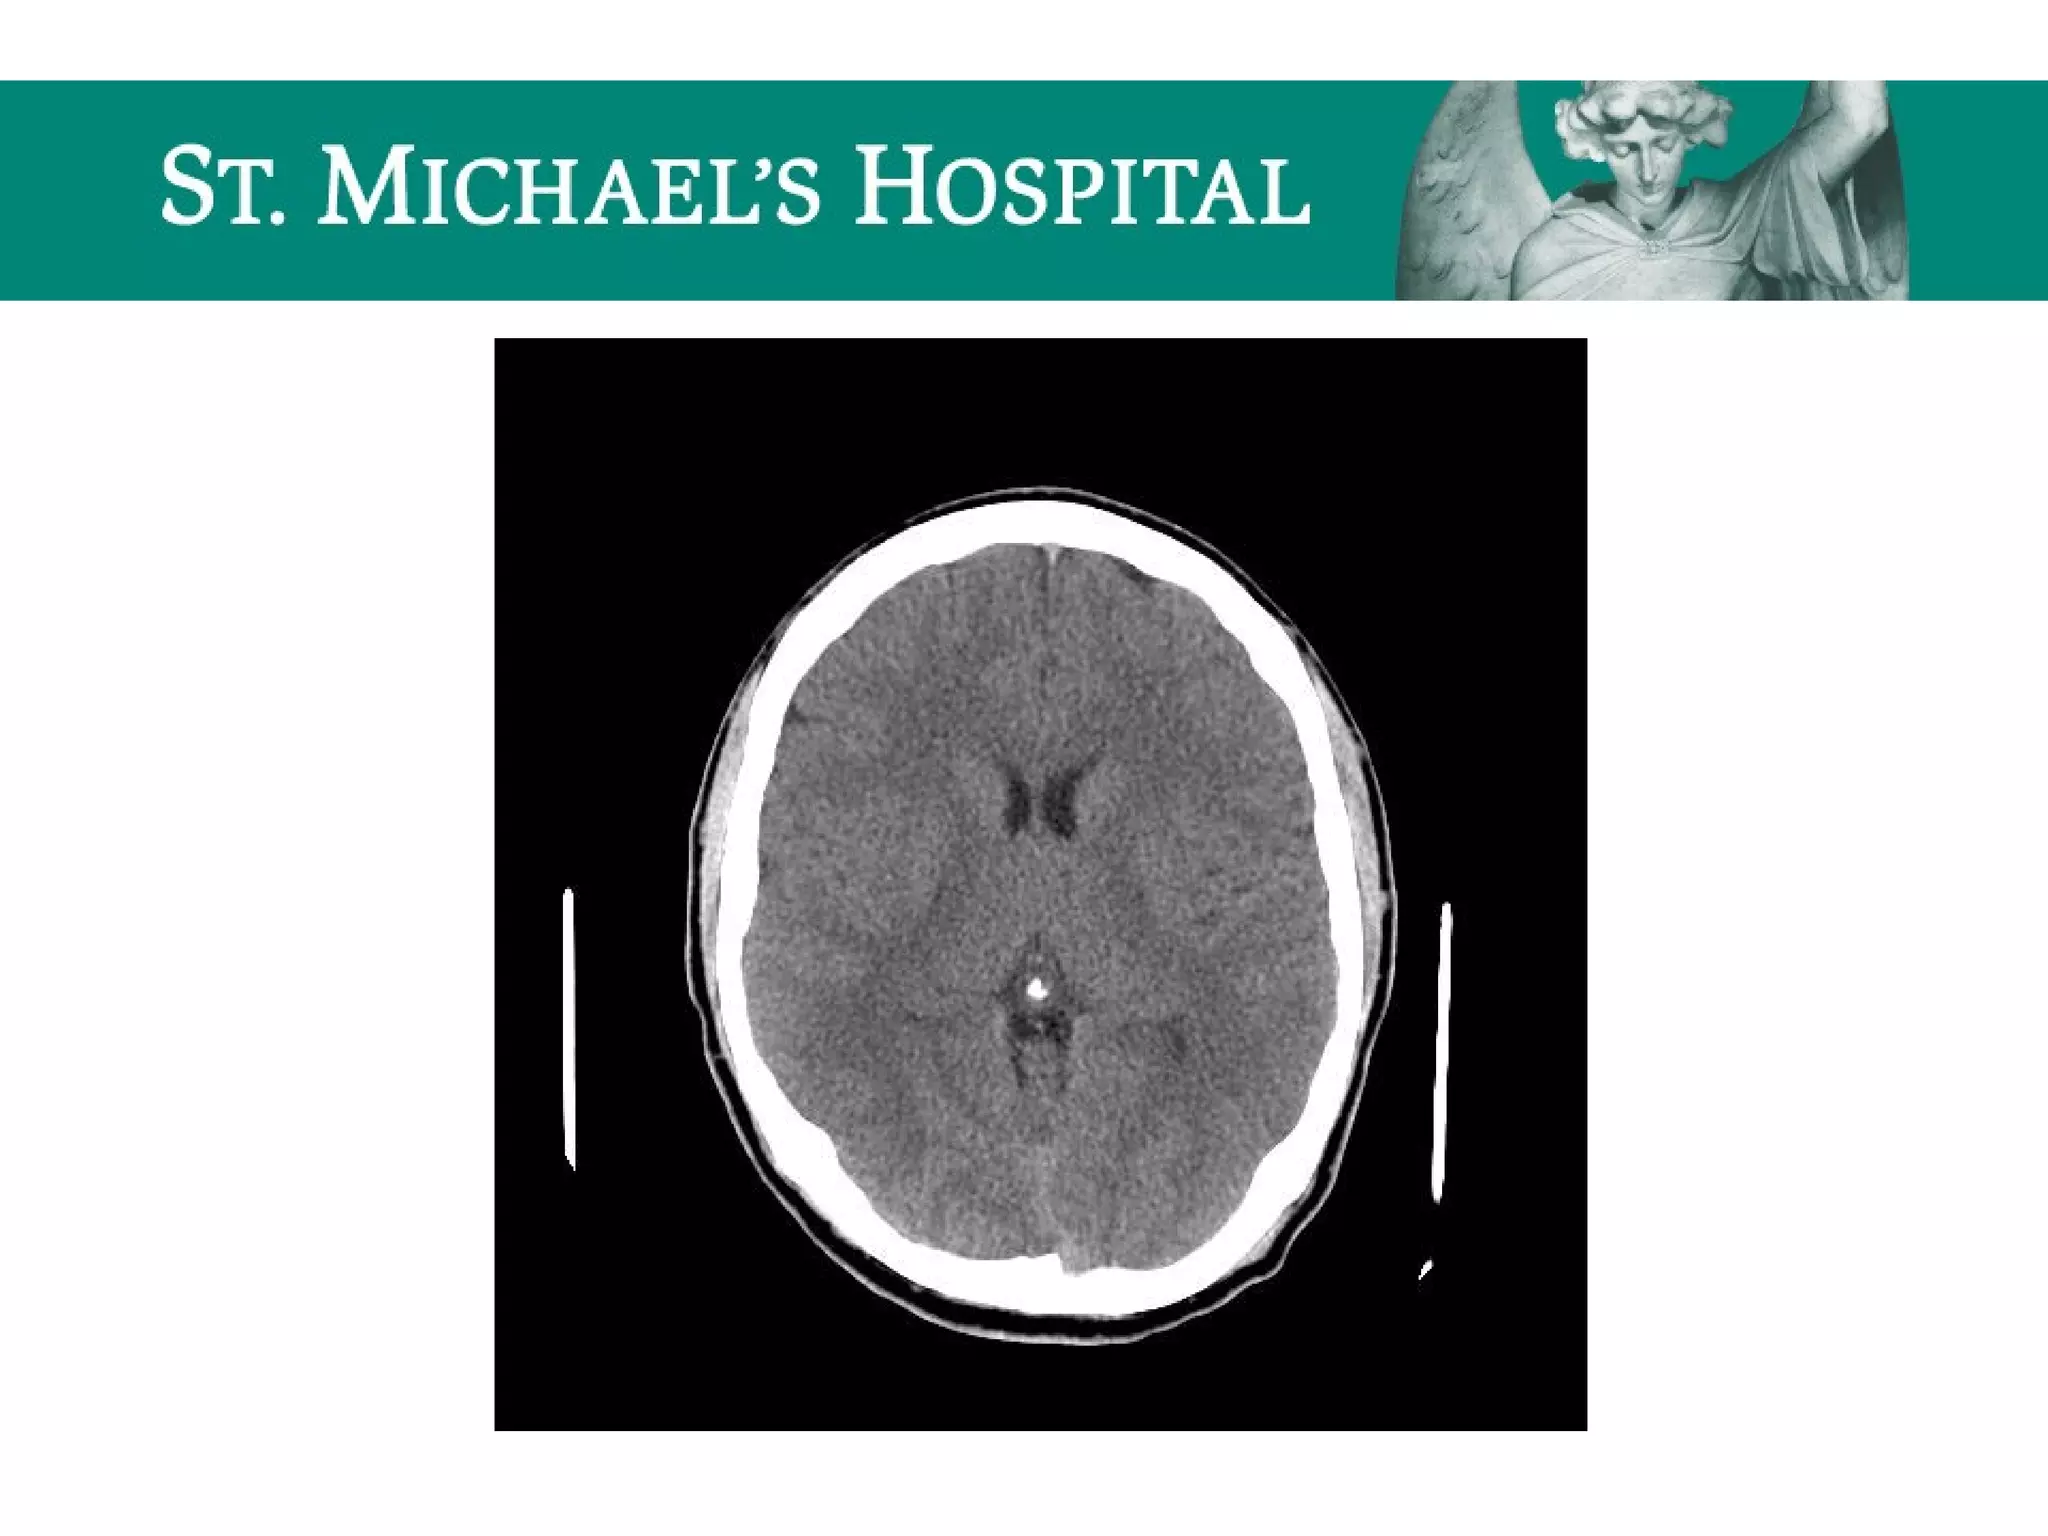

Diffuse Axonal Injury (DAI)

 Shear injury – secondary to severe rotational acceleration and

deceleration forces on the brain

 Unenhanced CT:

 Often normal (50-80%)

 Small hypodense foci due to traumatic edema

 Hyperdense petechial hemorrhages at the corticomedullary junction (20-50%)

 10-20% evolve to focal mass lesion (hemorrhage/edema)

 New lesions may become apparent on delayed scans

 Note: T2 GRE MR sequences are the most sensitive and demonstrate

hypointense foci at characteristic locations; microbleeds may only be

visible on GRE.

Diffuse Axonal Injury(DAI)  Shear injury – secondary to severe rotational acceleration and deceleration forces on the brain  Unenhanced CT:  Often normal (50-80%)  Small hypodense foci due to traumatic edema  Hyperdense petechial hemorrhages at the corticomedullary junction (20-50%)  10-20% evolve to focal mass lesion (hemorrhage/edema)  New lesions may become apparent on delayed scans  Note: T2 GRE MR sequences are the most sensitive and demonstrate hypointense foci at characteristic locations; microbleeds may only be visible on GRE.